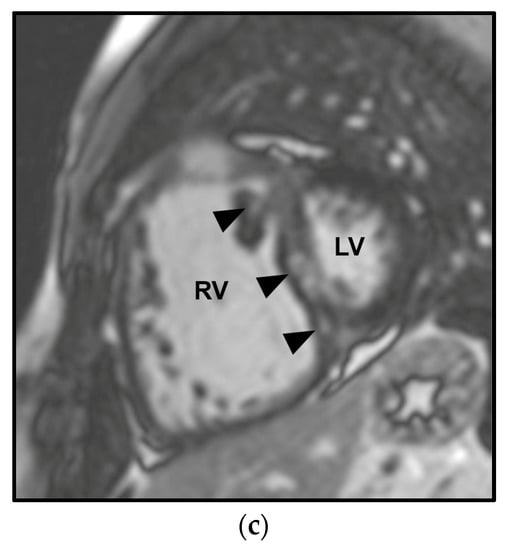

CMR allows high-resolution time-resolved three-dimensional (3D) volumetric imaging of the right heart, quantification of blood flow, detection of congenital cardiac malformation/abnormalities—including shunts—and visualization of myocardial fibrosis and scarring [5] (Figure 2 and Figure 3). Moreover, the use of combined contrast angio-MR and pulmonary perfusion imaging, together with late-enhancement imaging of the myocardium, provides a comprehensive picture of both heart and pulmonary vasculature [1]. A limitation is the absence of an established method to estimate PAP [1].

Cardiac magnetic resonance (CMR) in a patient affected by pulmonary arterial hypertension (PAH) in congenital heart disease with anomalous pulmonary venous return and intracardiac shunt. The Steady-state free precession (SSFP) in the four-chamber orientation in the diastolic phase shows marked dilation of the right ventricle (RV) and the compressed left ventricle (LV) (a). The SSFP in the short-axis orientation in the systolic phase depicts right ventricle dilation and leftward ventricular septal bowing (arrow) (b). The delayed enhancement CMR image (10 min post-gadolinium infusion) demonstrates mid-wall septal fibrosis and fibrosis at the anterior and posterior junctions between the septum and the RV free wall (arrowheads) (c).